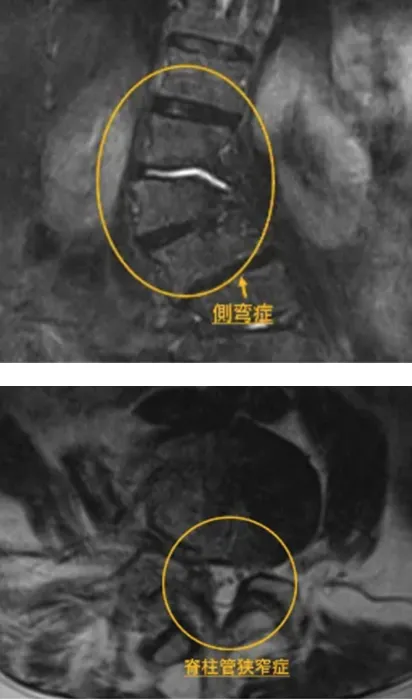

腰部脊柱管狭窄症・側弯症

以前より左臀部から足先にかけてしびれを自覚されており、近医で脊柱管狭窄症と診断されました。症状は徐々に悪化し、強い腰痛のために横になれず、座ったまま寝る生活が続いていました。医師からは手術を勧められましたが、「できる限り手術は避けたい」との強い希望をお持ちでした。

そのような中、ご家族の勧めでシンセルクリニックの再生医療を知り、半信半疑ながらも受診。カウンセリングにて治療内容や効果について丁寧な説明を受け、幹細胞治療を選択されました。

治療から約1か月後には腰痛と足のしびれがほとんど消失。横になって眠れるようになり、現在は旅行や外出も楽しめるまでに回復されました。

患者様は「手術を回避できて本当に良かった。自分の足で歩けることが何より嬉しい」と笑顔で話され、今後のさらなる改善にも期待を寄せておられます。

脊柱管狭窄症は、加齢や椎間板の変性によって脊柱管が狭くなり、神経を圧迫することで腰痛や下肢のしびれを引き起こす疾患です。進行すると歩行困難や睡眠障害を伴うこともあり、手術が検討されるケースも少なくありません。

幹細胞治療は、患者様ご自身の幹細胞を用いて神経や椎間板組織の修復を促す再生医療であり、炎症の抑制と血流改善を通じて神経症状の軽減を目指します。

本症例では、適切な診断と早期の再生医療により、手術を回避しながら疼痛としびれの大幅な改善が得られました。

手術に抵抗がある方や慢性的な腰・下肢症状でお悩みの方にとって、再生医療は新たな選択肢となり得る有効な治療法です。

幹細胞1億個 点滴1回

2カ月

以前から左臀部~足先のしびれがあり、最近は症状が悪化。近くの整形外科では脊柱管狭窄症と診断され、強い腰痛で横になれず、座ったまま寝る日々が続いていました。手術を勧められましたが、絶対に手術はしたくなかったため、なんとか別の方法で改善できないかと考えていました。

そんな時、家族がシンセルクリニックの再生医療があることを教えてくれ、最初は半信半疑で連絡しました。カウンセリングで詳しい説明を受け、手術を回避できる可能性があると知り、再生医療を受けることを決断しました。

治療後1ヶ月で腰の痛みと足のしびれがほとんど消失し、今では横になってしっかり眠れるようになりました。手術を回避できたことが本当に嬉しく、再生医療を選んでよかったと心から思っています。また、趣味である遠出や友人との旅行も楽しめるようになり、自分の足でしっかり歩ける喜びを実感しています。